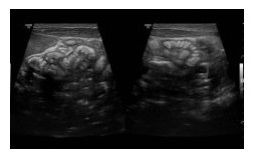

Các kết quả cận lâm sàng cho thấy trẻ có các quai ruột hẹp, thành tăng âm, đoạn dài ~110mm giãn căng, đường kính lớn nhất 48mm, trong lòng chứa nhiều dịch. Qua hội chẩn chuyên khoa, các bác sĩ đánh giá đây là ca mổ khó khăn vì trẻ non tháng, cân nặng thấp, chức năng hô hấp tuần hoàn chưa hoàn chỉnh. Tuy nhiên, phải quyết định mổ khẩn cấp để thông suốt chỗ ruột tắc, tránh để xoắn hay hoại tử ruột, nhiễm trùng nhiễm độc toàn thân diễn biến nhanh.